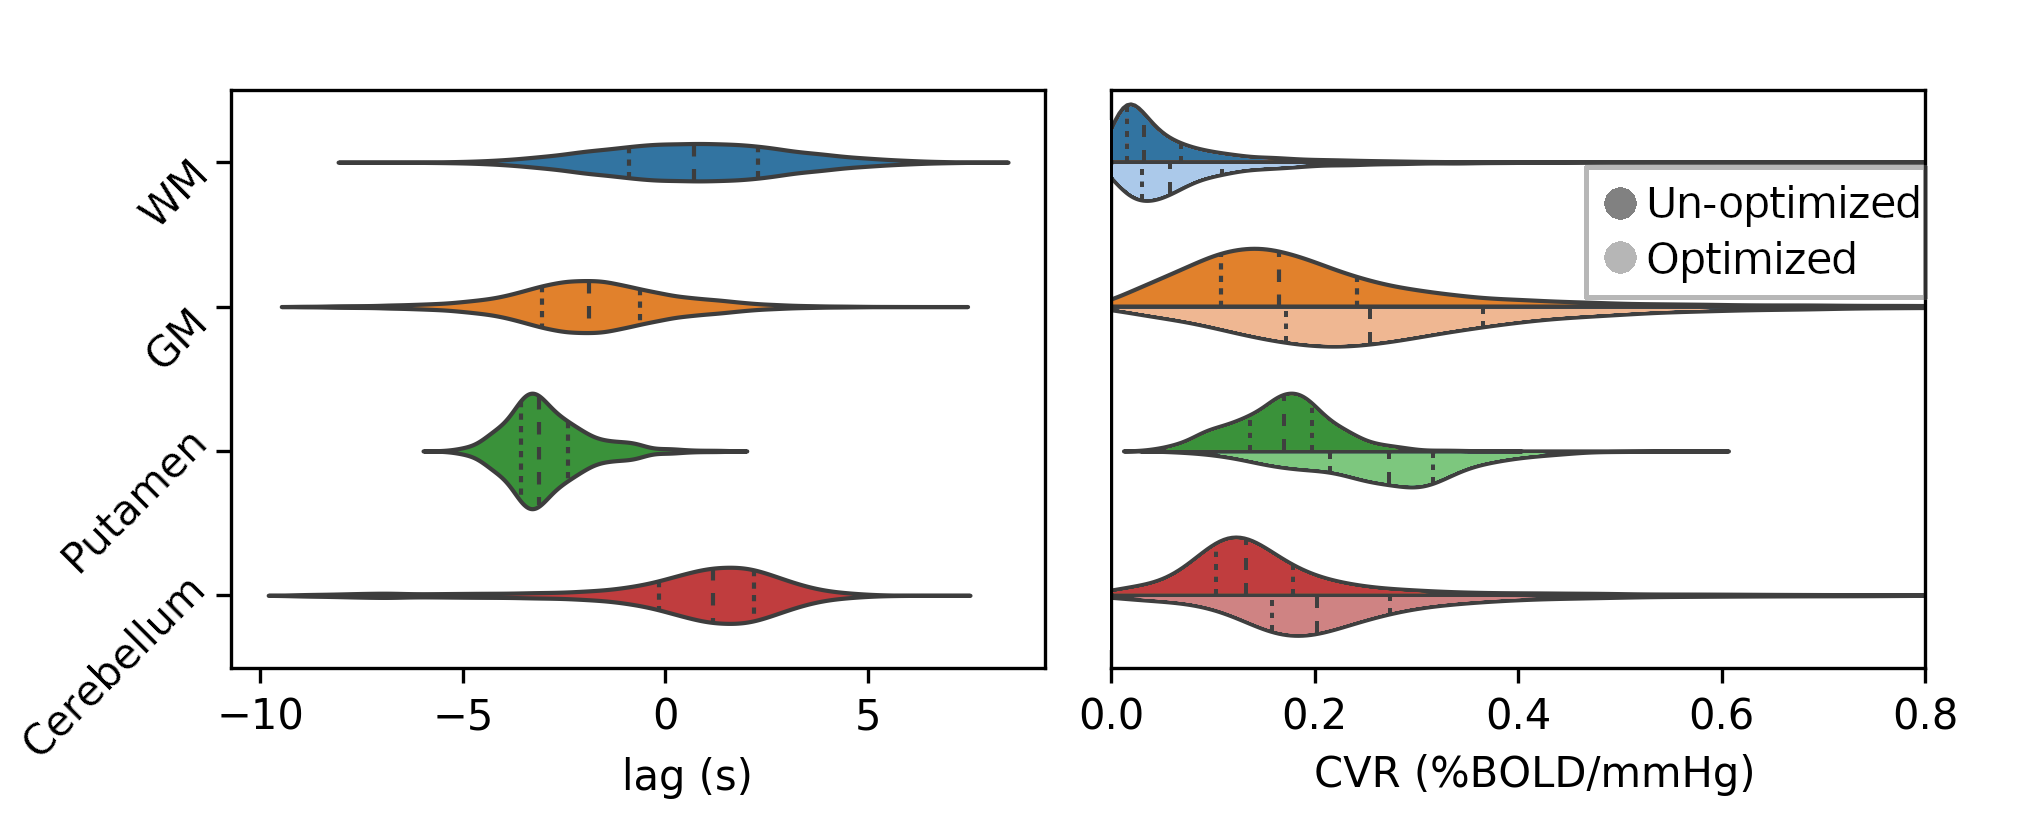

Results: lag optimisation

Non optimising leads to underestimate the CVR, especially in subcortical areas.

Lag maps show anatomical consistency

Different lag responses, coherent with previous evidence (e.g. Putamen has earlier response than GM)

Results: CVR amplitude maps

Moia et al. 2021 (NeuroImage)

Results: lag maps

Moia et al. 2021 (NeuroImage)